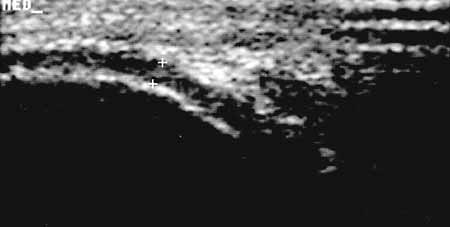

Рис. 6. Коленный сустав в норме. Поднадколенниковая область, сагиттальная

проекция; гиалиновый хрящ медиального мыщелка бедренной кости в норме (+).